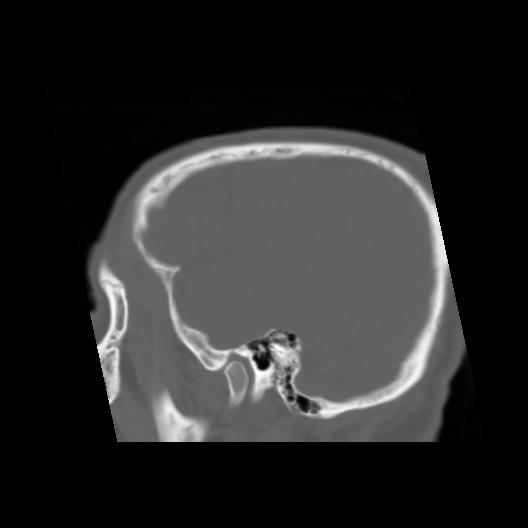

6 CEREBRO,,Sagittal,3.000,CEREBRO,Sagittal,